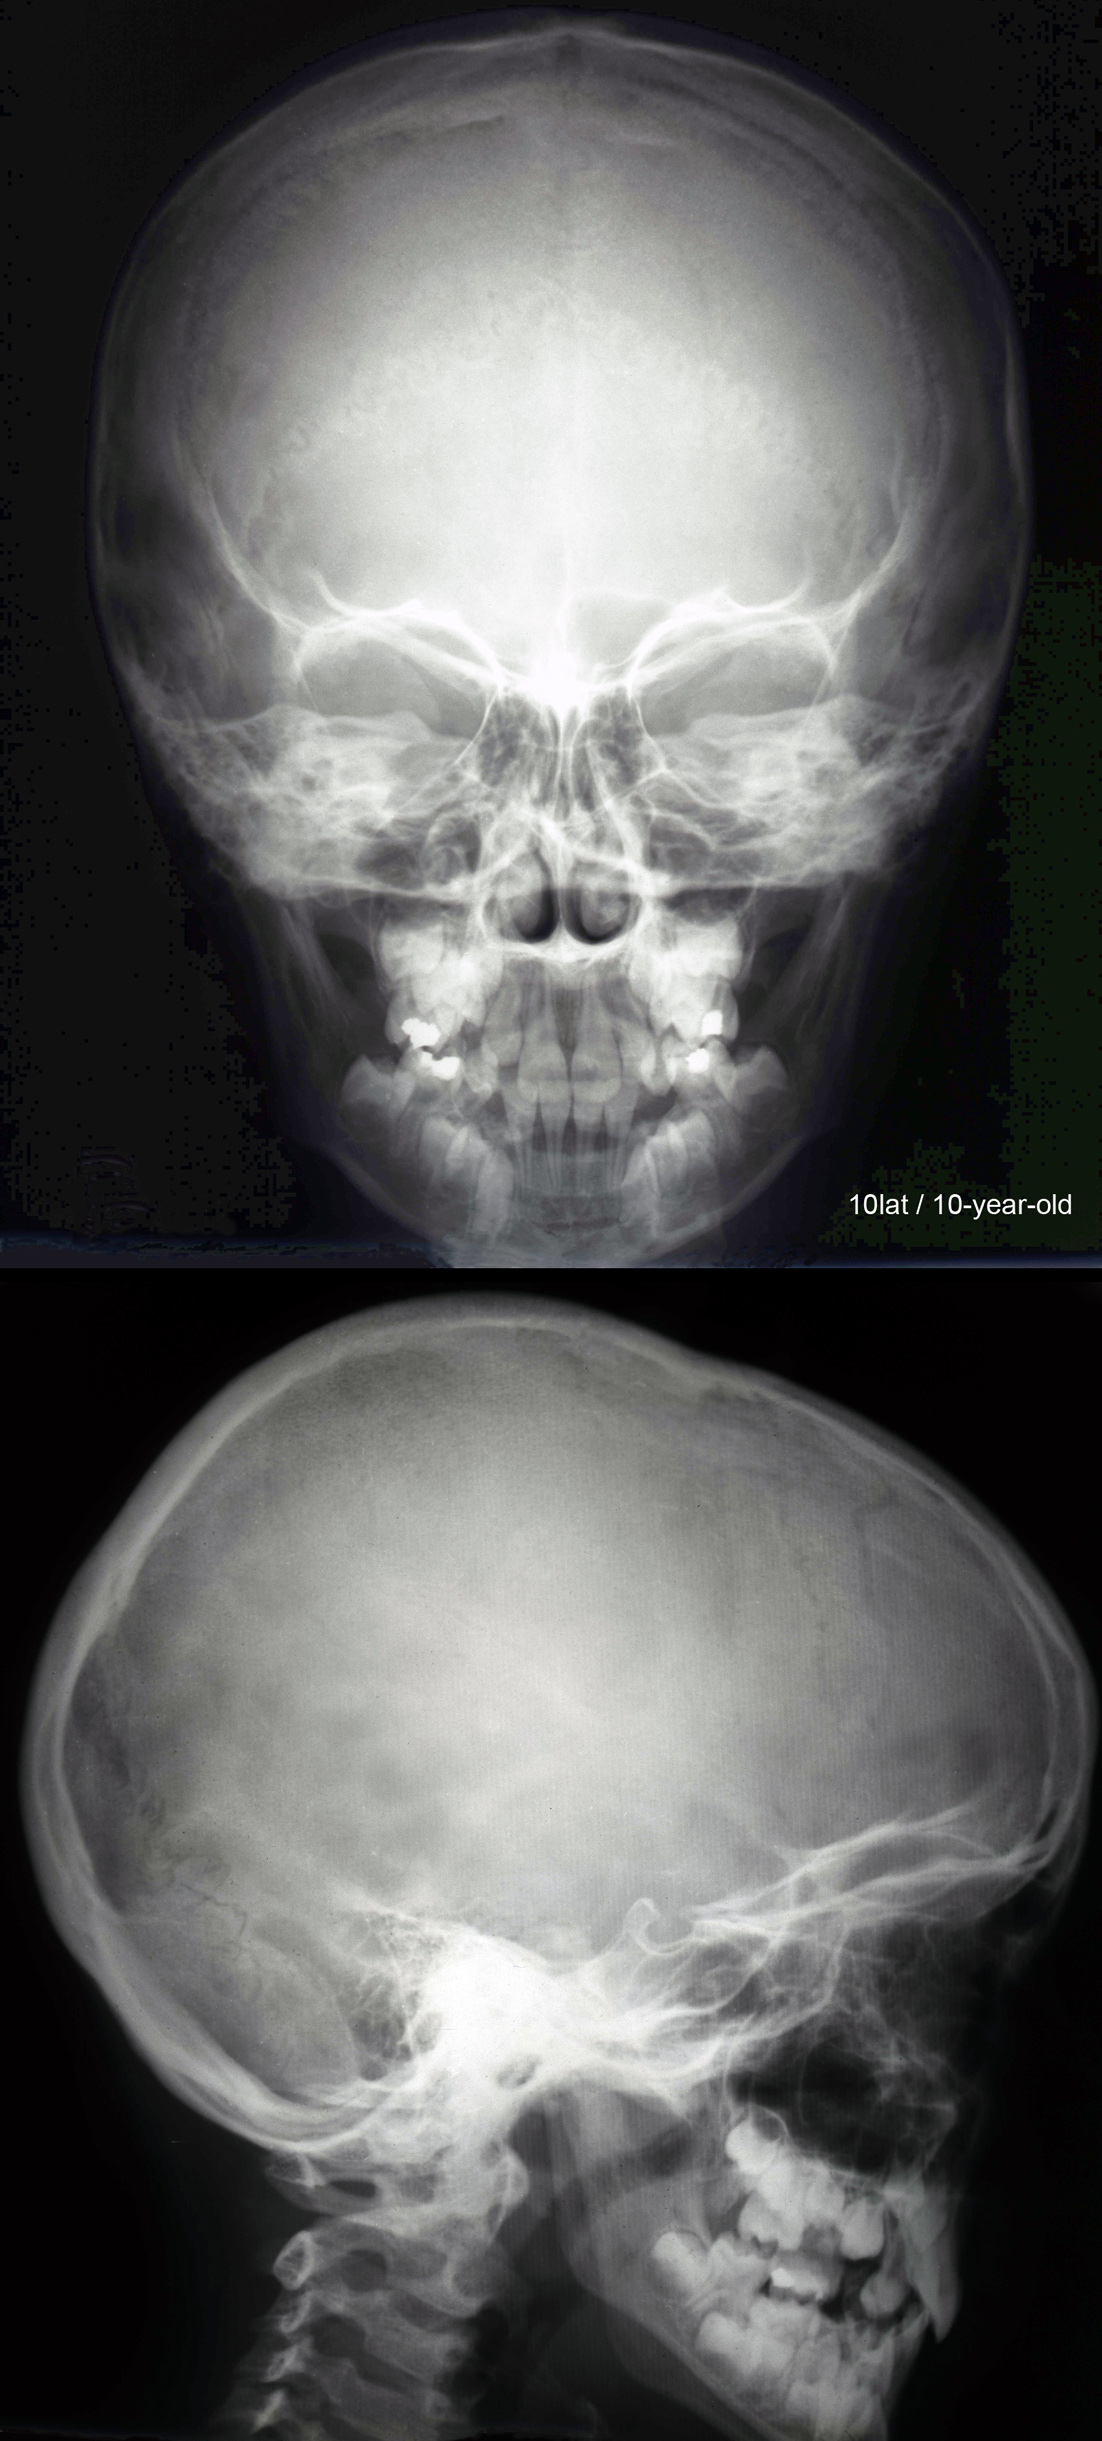

RTG głowy 10-letniego dziecka..

. RTG głowy dziecka w okresie

od 2 do 10 roku.